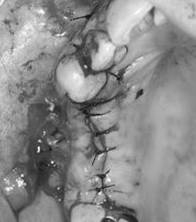

Khi bạn ghép Implant, BS có thể lật nướu để bộc lộ xương hoặc không lật nướu, từ chuyên môn gọi là lật vạt. Nếu bạn ghép Implant đồng thời phải thực hiện thủ thuật rạch nướu để lật vạt, thì cần phải dành nhiều thời gian để lành thương hơn. Chính thủ thuật này làm cho vết thương lâu lành hơn.

Hình: cùng cấy ghép 3 Implant, nhưng ở hình bên trái kỹ thuật rạch nướu và lật vạt sẽ gây ra nhiều chấn thương, và thời gian lành thương lâu hơn so với kỹ thuật “không lật vạt” ở hình bên phải.